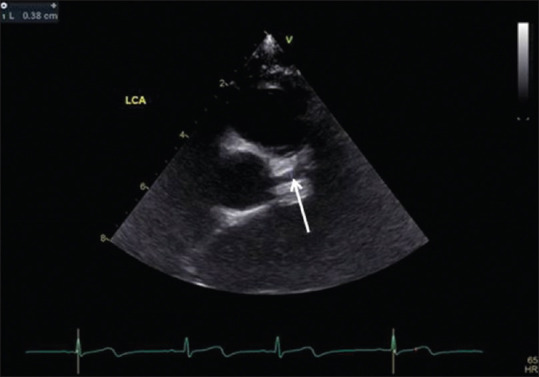

川崎病(Kawasaki disease, KD)是一种病因不明的儿童多器官和系统的全身性炎症性疾病。基本的病理改变是中小动脉,主要是冠状动脉的全血管炎。它现在是发达国家儿童获得性心脏病的主要原因,并导致心绞痛、心肌缺血/梗死的早期发展,甚至是成年早期的心源性猝死。虽然对KD没有明确的诊断测试,但准确的诊断取决于临床表现是否符合诊断标准。超声心动图是一种众所周知的无创工具,用于检测结构异常和评估心血管功能。据报道,它可以准确地检测早期和晚期心血管异常,包括血管周围亮度,缺乏锥形,扩张和冠状动脉动脉瘤形成以及二尖瓣/主动脉反流,心包积液和KD的心肌功能改变。对于KD形态不全及临床表现不符合诊断标准的患者,冠状动脉超声心动图异常可为KD的早期诊断提供帮助。长期定期超声心动图随访是KD患者首发冠状动脉异常的基础和必要研究。本文回顾并讨论了99篇研究KD超声心动图表现的文章。

Kawasaki disease (KD) is an etiology-unknown but with a generalized inflammatory disorder of multiple organs and systems in childhood. The basic pathologic changes are panvasculitis of the small and medium-sized arteries, mainly the coronary arteries. It is now the leading cause of acquired heart disease during childhood in developed countries and has led to the early development of angina pectoris, myocardial ischemia/infarction, and even sudden cardiac death in early adulthood. Although there is no definitive diagnostic test for KD, the accurate diagnosis is dependent on the clinical presentations to meet the diagnostic criteria. Echocardiography is a well-known noninvasive tool to detect structural abnormalities and evaluation of cardiovascular function. It has been reported to detect accurately the early and late cardiovascular abnormalities, including perivascular brightness, lack of tapering, dilatation, and aneurysmal formation of coronary arteries as well as the mitral/aortic regurgitation, pericardial effusion, and myocardial functional changes in KD. In cases of incomplete form of KD and patients whose clinical manifestations did not meet the diagnostic criteria, abnormal echocardiographic findings of coronary artery may provide the assistance for early diagnosis of KD. Long-term periodic echocardiographic follow-up is the basic and essential study for patients of KD with initial coronary arterial abnormalities. Ninety nine articles that studied echocardiographic findings of KD had been reviewed and will be discussed.